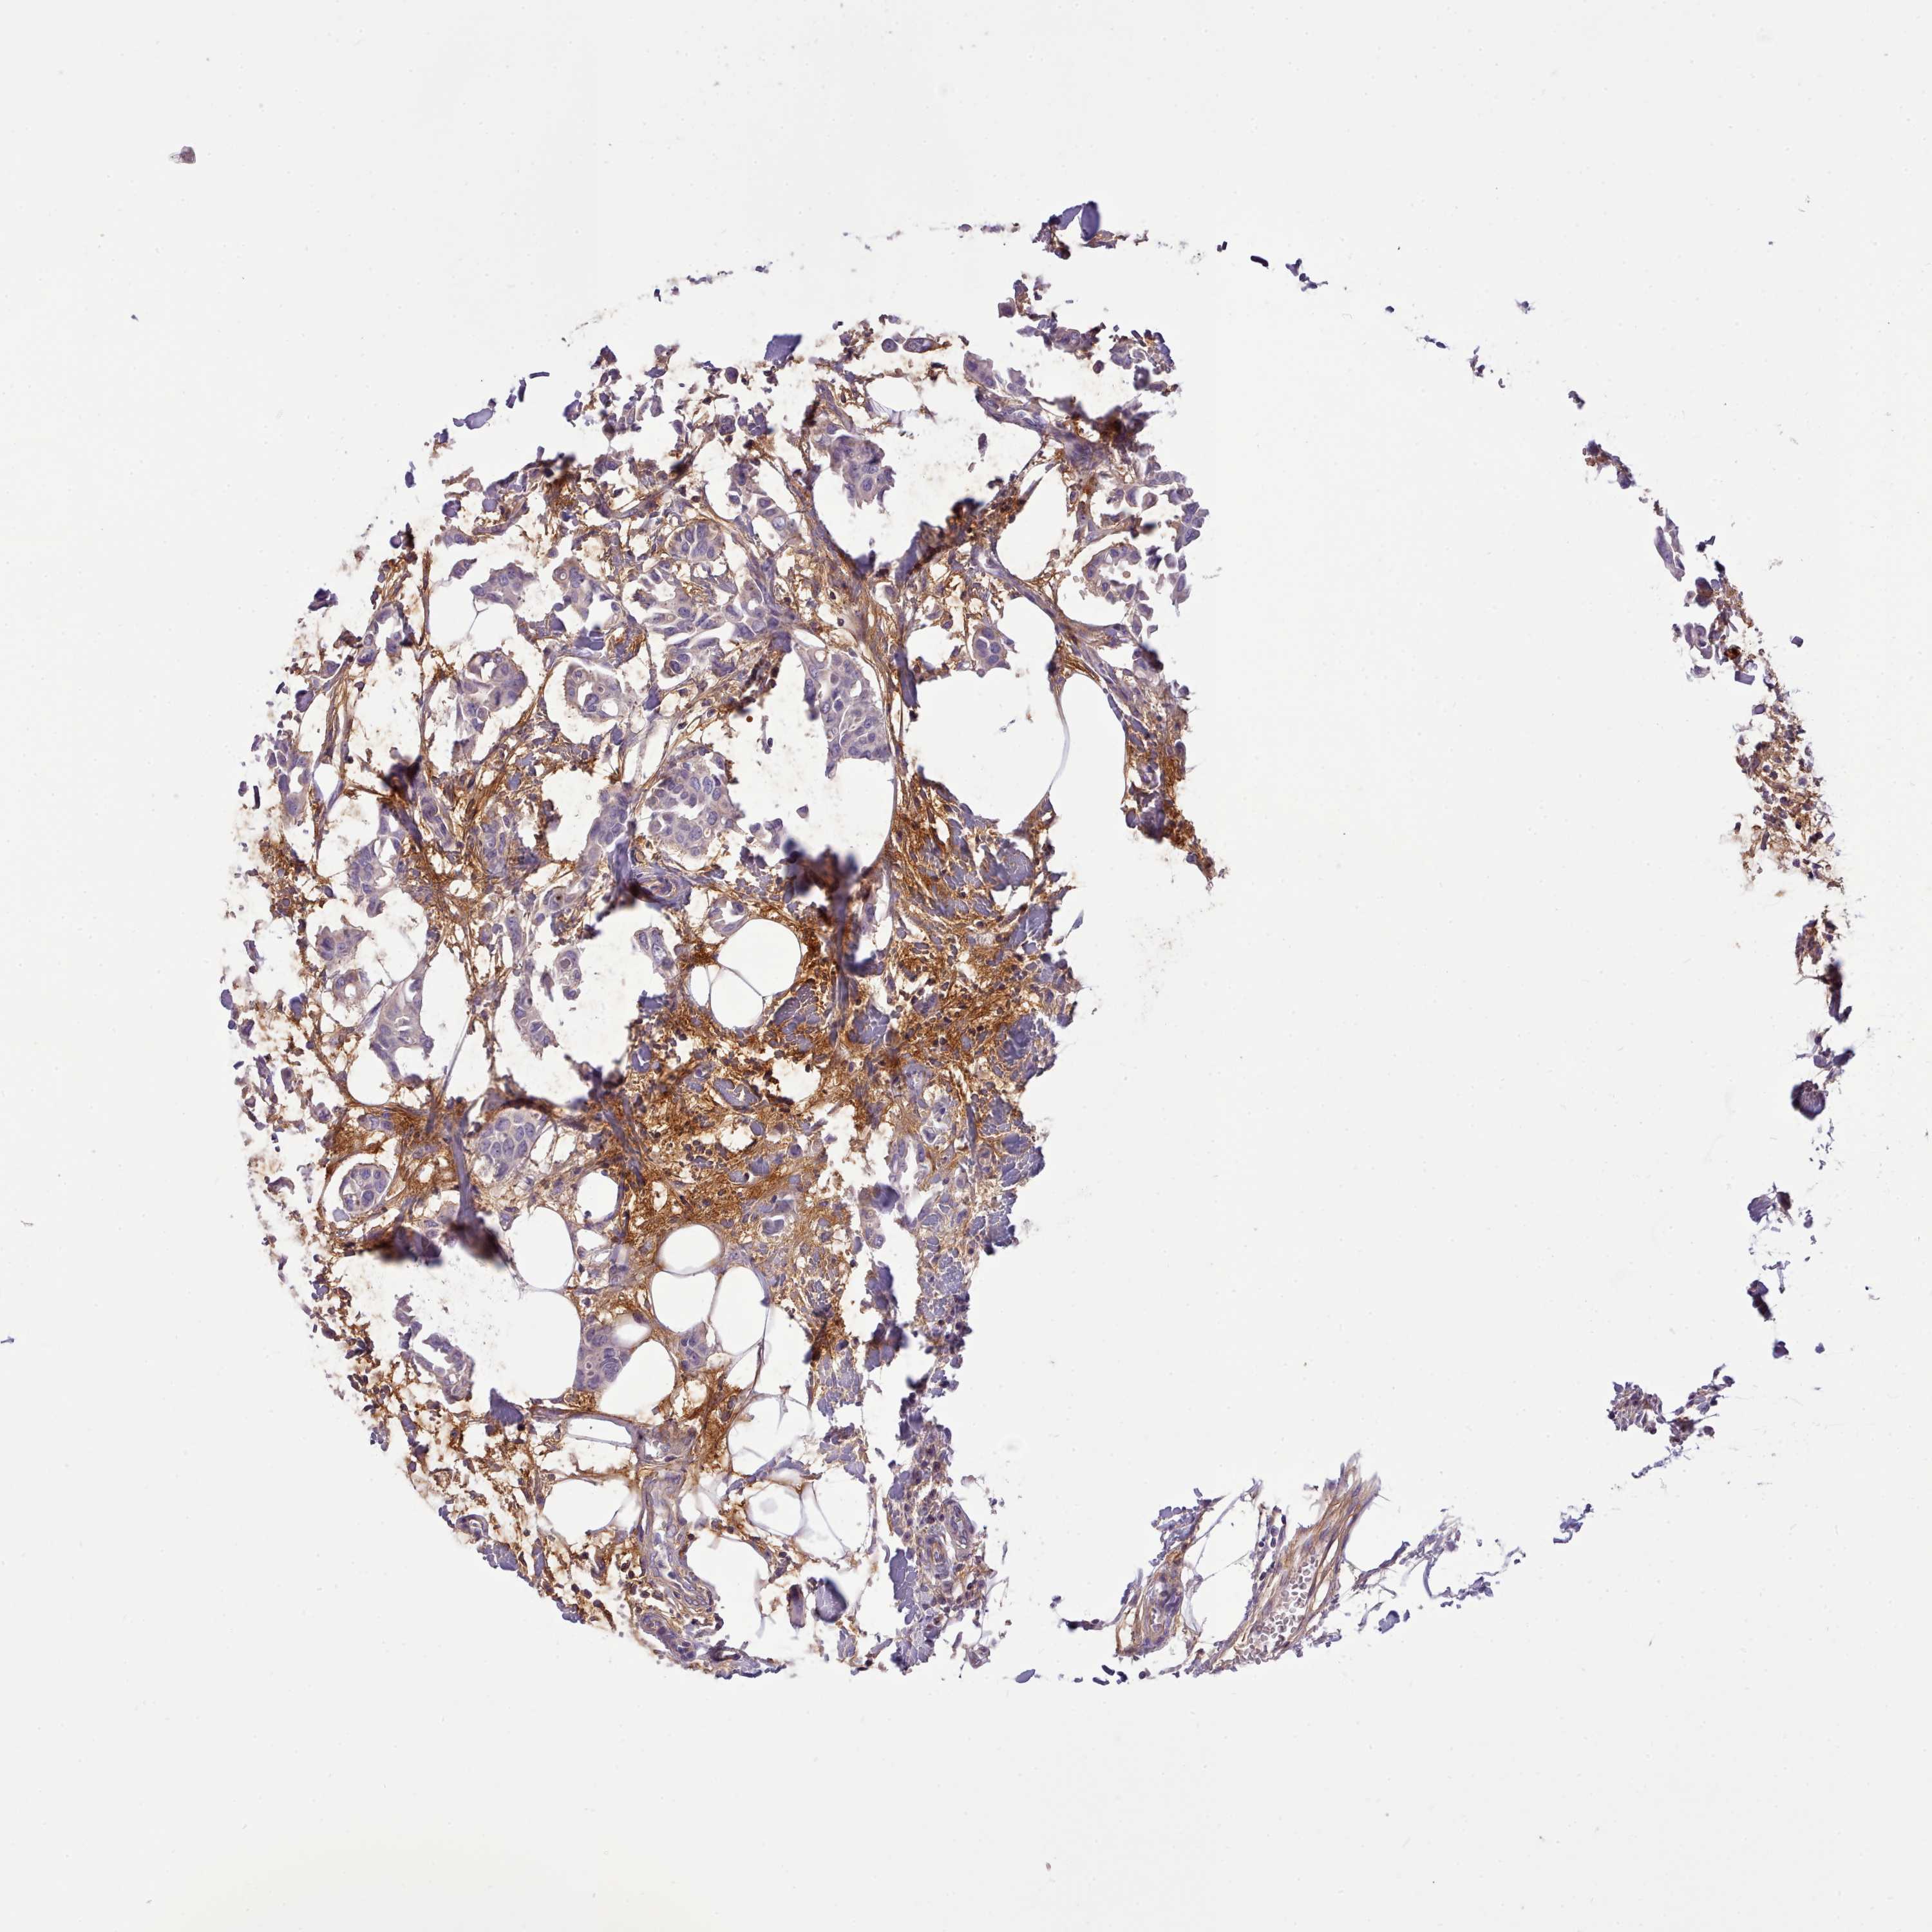

CANCER BREAST CANCER Show tissue menu

BRCA TCGA BRCA VALIDATION PROTEIN EXPRESSION

ANTIBODIES

AND

VALIDATION